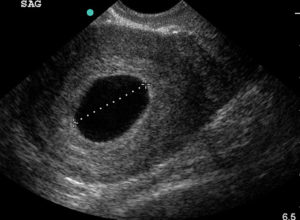

Так на УЗИ выглядит пустое плодное яйцо.

Пустое плодное яйцо – это по сути беременность, которая не начала развиваться. Процесс развития прекратился еще до этапа формирования эмбриона. Причин такого нарушения достаточно много.

На ранних сроках крайне сложно выявить пустое плодное яйцо. Так как размеры эмбриона очень малы и его можно просто не заметить. Только по прошествии 5 недель, появляется возможность определить отсутствие плода.

Только на шестой неделе беременности пустое плодное яйцо можно диагностировать с помощью УЗИ. Оно проводится в любом случае, чтобы определить месторасположение плода, а также исключить внематочную беременность.

Определить анэмбрионию по УЗИ можно не ранее 5-6 недель беременности, но и на этом сроке могут быть ошибки.